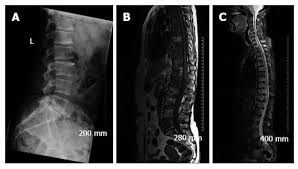

False Positive Diagnosis Of Disease Progression By Magnetic Resonance Imaging For Response Assessment In Prostate Cancer With Bone Metastases A Case Report And Review Of The Pitfalls Of Images In The Literature

False Positive Diagnosis Of Disease Progression By Magnetic Resonance Imaging For Response Assessment In Prostate Cancer With Bone Metastases A Case Report And Review Of The Pitfalls Of Images In The Literature from www.spandidos-publications.com